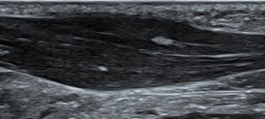

Using a real-world example, eccentric training has shown efficacy in healing Achilles tendinopathy. One study followed 25 patients with chronic Achilles tendinopathy. The mean age was 50 years old and they had suffered on average for 17 months. They were given a 12 week eccentric achilles exercise program. Eccentric, meaning that the exercise focused on slowly lowering the heel downward from a heel raise. Basically, standing on a stair, coming up on your heels using both feet, then slowly lowering down only on the painful side. At a mean follow up of 3.8 years, 22 of the 25 patients satisfied with the outcome. Even more interestingly, 19 of the 26 tendons followed by musculoskeletal ultrasound imaging showed a normalization of tendon structure4.

Musculoskeletal ultrasound images of a painful Achilles tendon (a) showing a thickened tendon with areas of poor tissue quality and images of a normal Achilles tendon (b)

What is the reason these anatomical changes occurred and could be seen clear as day on the ultrasound images? Of course, it’s mechanotransduction!